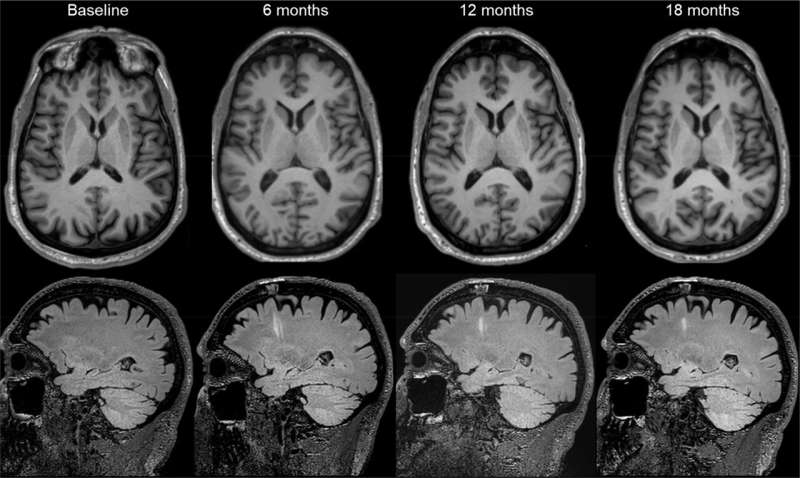

代表性磁共振圖像。圖片來源:《自然》(2025)。DOI:10.1038/s41586-025-08845-y

該研究還探討了這種療法是否對患者的病情有任何影響。治療兩年后,六名可評估的參與者在臨床醫生用來衡量帕金森病運動癥狀嚴重程度的量表上有所改善。研究人員觀察了所謂的“開”時間(即藥物充分控制這些癥狀的時間)以及相反的“關”時間,發現評分平均分別提高了36%和20%。